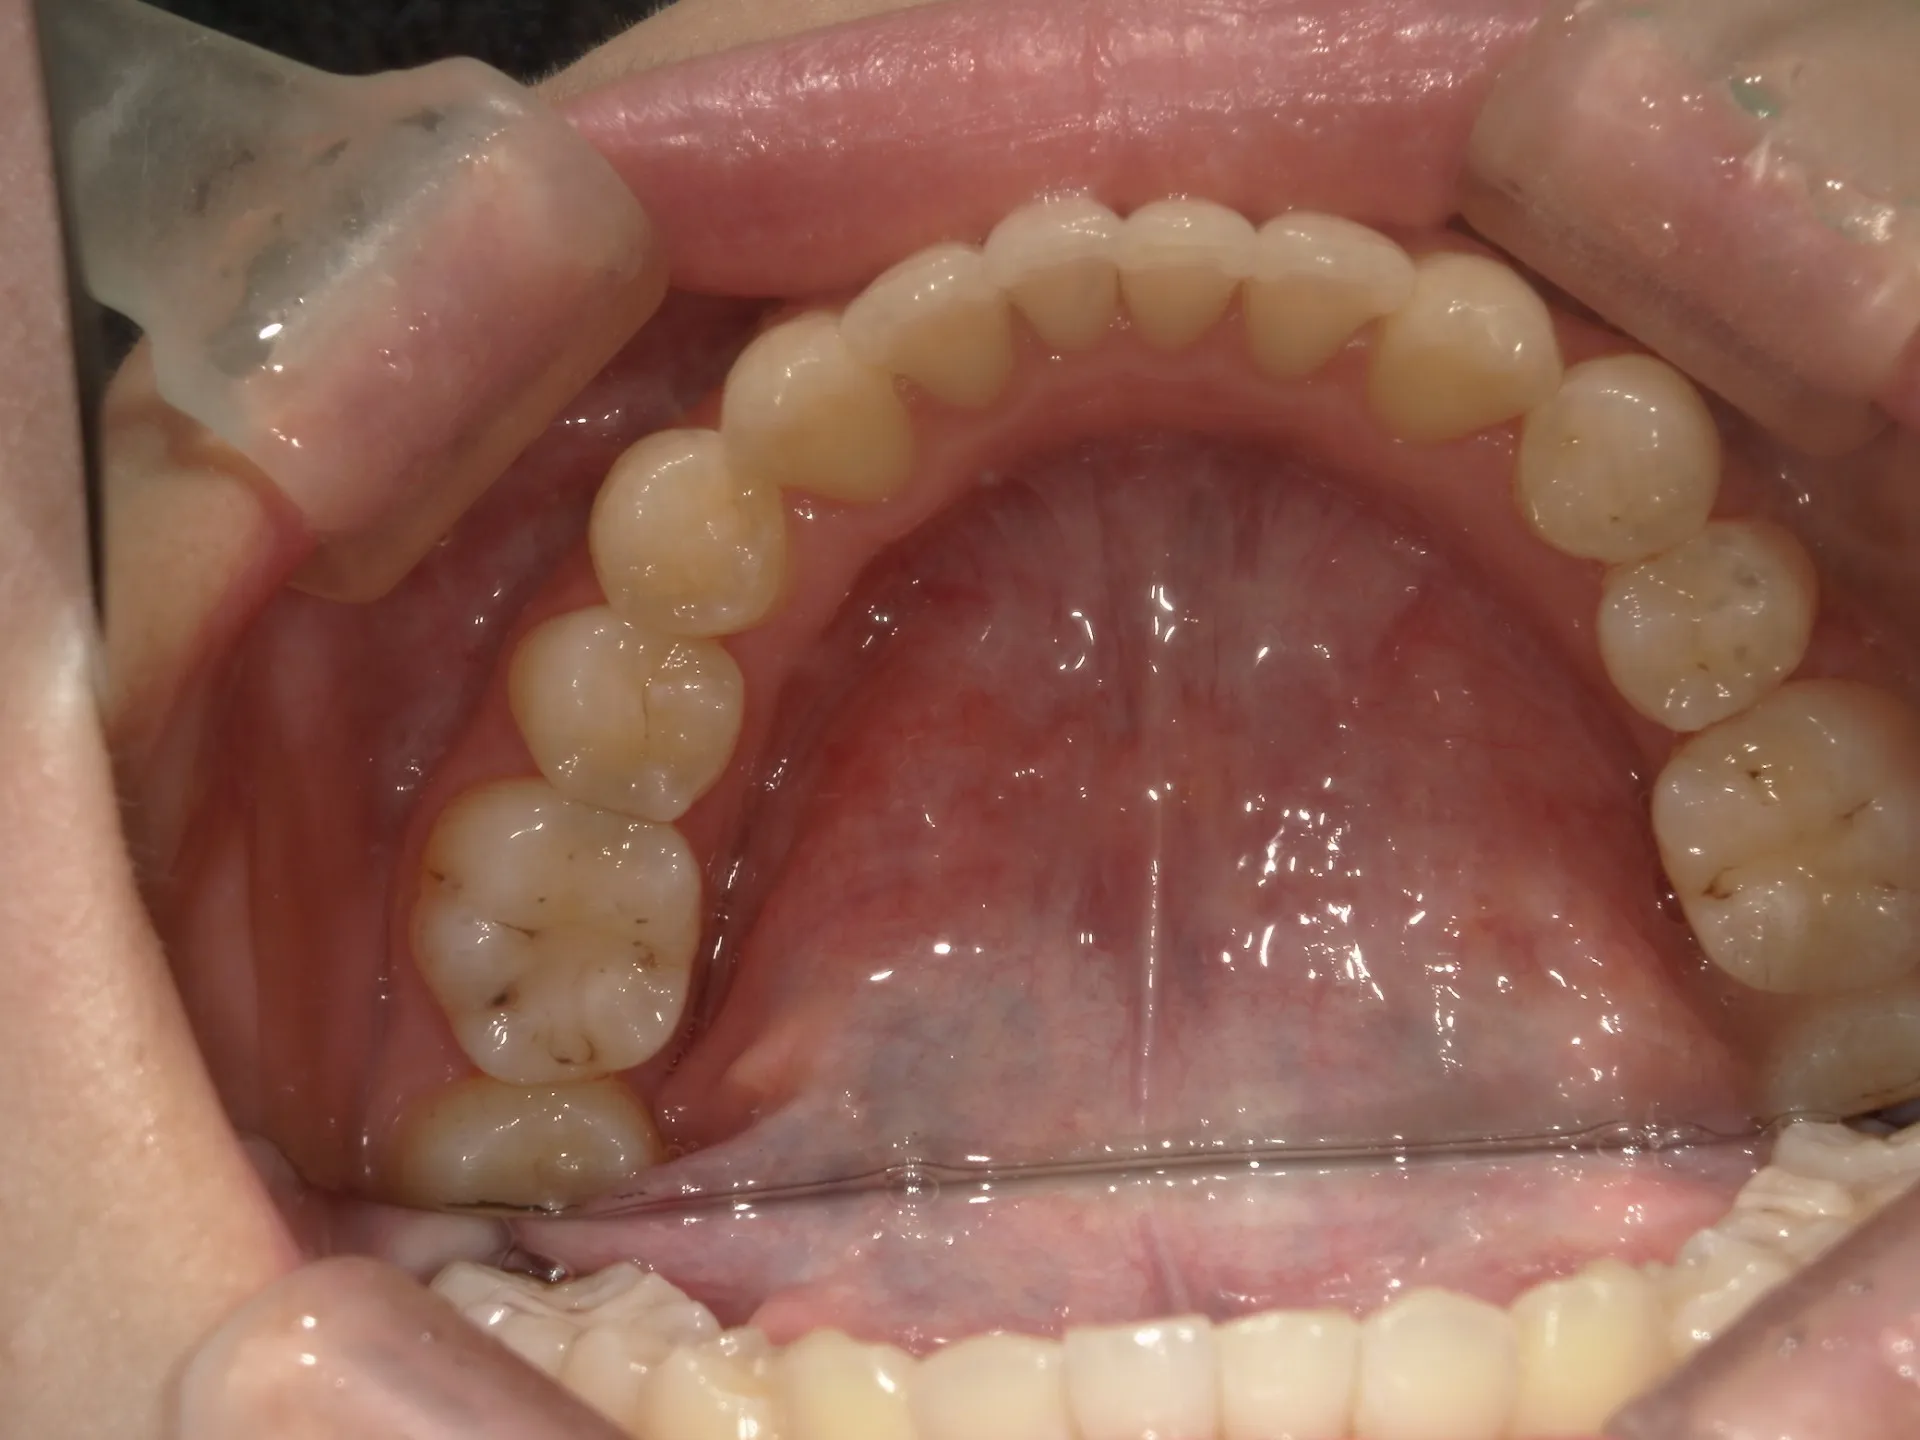

今回はマウスピース矯正(インビザライン)で前歯の出っ張りを治したケースをご紹介いたします。

マウスピース矯正で前歯の出っ歯感を抑えることが可能で、このケースでは上の歯のみ2本の抜歯を行っています。